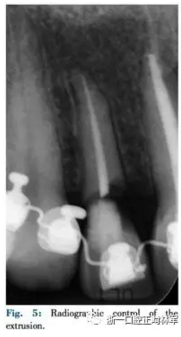

該患者使用舌側(cè)全口間接粘接,部分牽引12,使用0.016TMA銅鎳鈦絲(圖3,4,5)。開(kāi)始階段實(shí)現(xiàn)緩慢牽引使12頰側(cè)齦緣更接近切端,隨后采用纖維環(huán)切術(shù)進(jìn)行快速牽引以暴露損害邊緣(圖6)。

正畸牽引結(jié)束(圖7)時(shí),皮瓣抬高后使用橡皮障暴露邊緣(圖8),進(jìn)行纖維樁修復(fù),堆好核后使用層壓瓷貼面修復(fù)(圖9-11)。